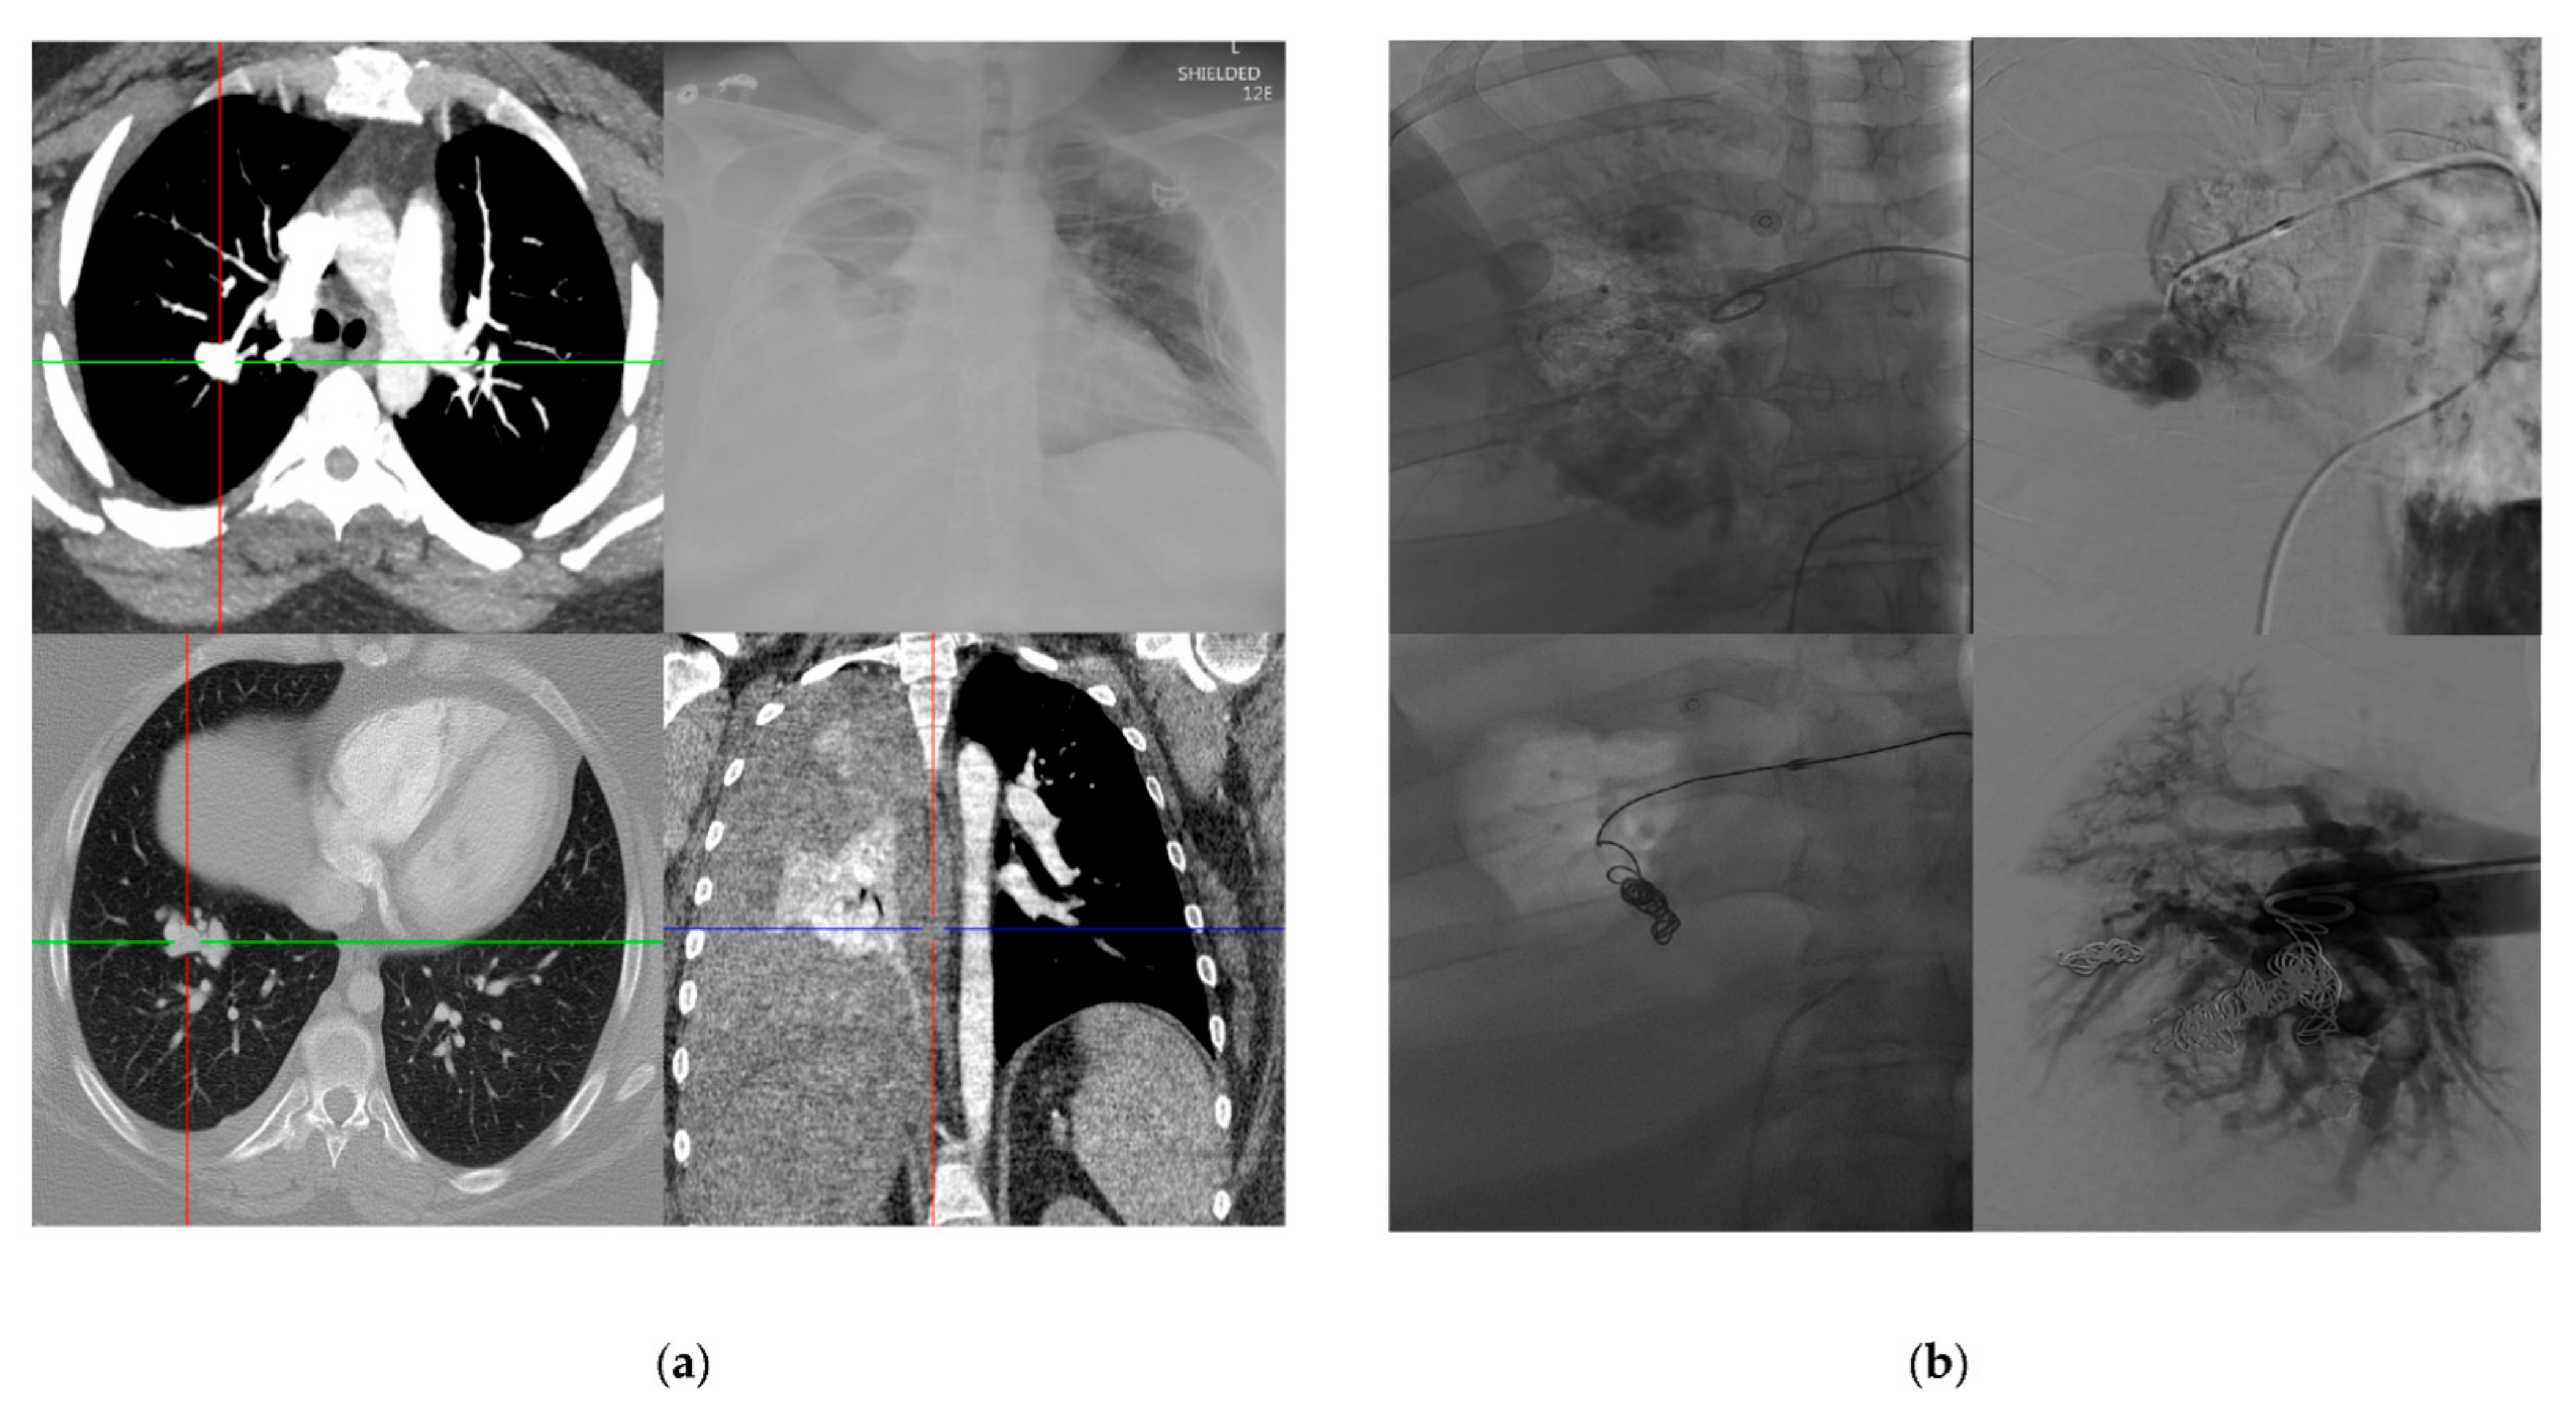

3.4. Lesion Characterization

3.5. Treatment Outcomes